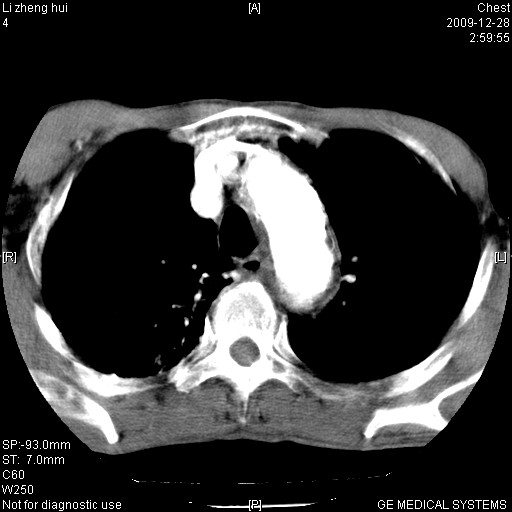

标题: CT23859:胸主动脉瘤

男  79岁 胸部痛急诊入院,晚上做的增强

考虑主动脉瘤?(增粗、钙化、壁血栓?)

支持降主动脉夹层

支持降主动脉瘤,不考虑夹层

1)考虑胸主动脉壁间血肿或夹层动脉瘤。2)多发性肝囊肿。

1)考虑胸主动脉附壁血栓或夹层动脉瘤。2)多发性肝囊肿。